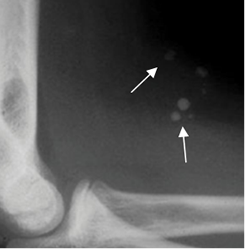

Fig 4A. Calcificaciones en los tejidos blandos.

Rx lateral. Prominencia de los tejidos blandos de la parte anterior del codo, con calcificaciones que corresponden a flebolitos, por un hemangioma.